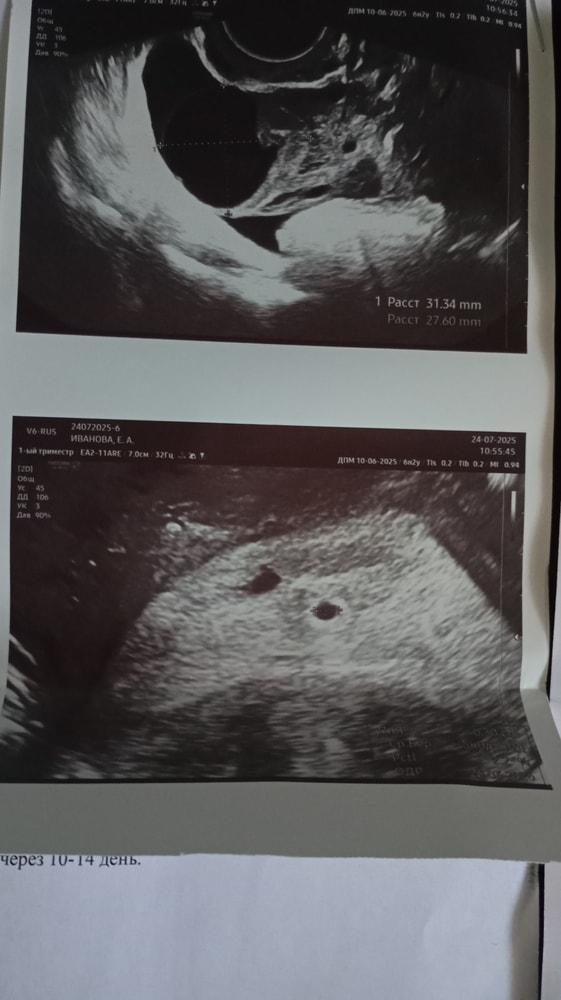

1е УЗИ от 24го - ПЯ 3мм, срок по узи 5.0

2е УЗИ от 31го - ПЯ 9мм, ЖМ 3.8, эмбриональный бугорок 2.5. срок по узи 5.5